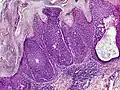

Microscopic histopathological examinations of the tumor tissues of all poroma variants stained with hematoxylin and eosin dyes reveal: a) basophilic "poroid cells" (i.e. small, cuboid-shaped cells with oval nuclei which resemble cells in the peripheral layer of the distal portion of eccrine sweat gland ducts[20]) that may form cords and broad columns extending downward from the epidermis; b) larger cuticular cells (i.e. squamous epithelial-like eosinophilic cells that resemble the luminal cells lining eccrine sweat gland ducts[20]); and in some cases c) clear cells (i.e. cells with small nuclei surrounded by pale cytoplasm).[3] Poroma tumor tissues may appear highly vascularized and/or have areas of necrosis, i.e. dead or dying cells. Hidroacanthoma simplex variants are mainly composed of poroid cells, few cuticular cells, and no clear cells and are confined to the epidermis; dermal ductal variants are mostly confined to the superficial dermis and are composed of small solid and cystic nodular aggregates of poroid, cuticular, and clear cells; poroid hidradenoma variants have large aggregates of solid and cystic components and extend deeper into the dermis or even subcutis; and eccrine poroma variants are composed of all three cell types but are primarily located in the epidermis and superficial dermis. Poromas may have 2 or more of these variants in the same tumor tissue and the variants typically have histopathology findings that are not clearly distinguishable from each other.[3]

Eccrine poroma